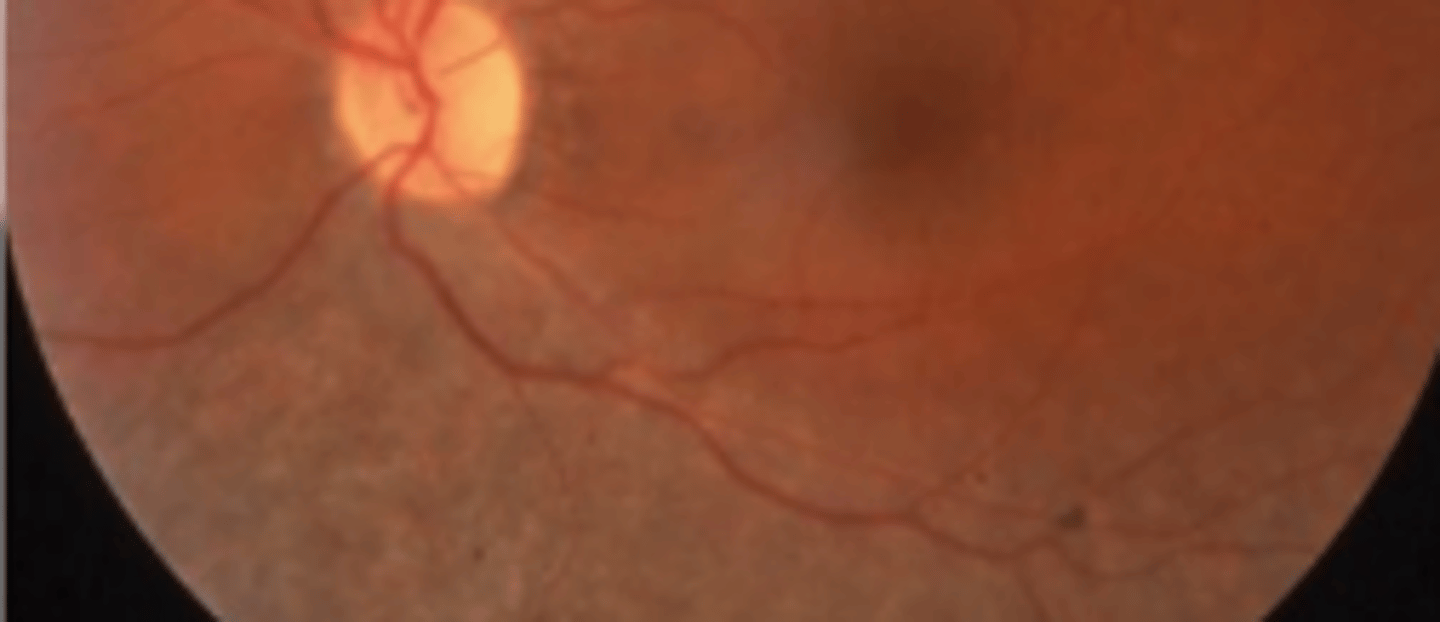

Choroideremia

an X linked progressive diffuse degeneration of the choroid, RPE, and retinal photoreceptors. Presents in the 2nd-3rd decade with nyctalopia and constricted visual fields. Central vision is spared up until the 6th decade, prognosis is poor. ERG and EOG subnormal. VF shows annular scotomas that eventually involve fixation.

Gyrate atrophy

an autosomal recessive condition resulting in a metabolic defect due to mutation of the ornithine degradation enzyme. Leads to a buildup of ornithine in plasma, urine, CSF, and aqueous. Presents as a reduction in peripheral and night vision. Patches of choroiretinal atrophy coalesces to form scalloped lesions. Spares the fovea until late disease (4th-5th decade), prognosis is poor. Treatment includes pyridozine (vitamin B6) and limitation of arginine intake (low protein).

Central areolar choroidal dystrophy (CACD)

an autosomal dominant condition resulting in progressive significant vision loss due to a mutation in the peripherin 2 (PRPH 2) gene. Progresses in stages, but appears extremely similar to AMD throughout making it difficult to diagnose. Presents as decreased vision and scotoma. Low vision referral and genetic testing indicated.

Younger presentation (3rd-4th decade), sharp decrease in vision (5th-7th decade), no drusen

three factors differentiating central areolar choroidal dystrophy from AMD